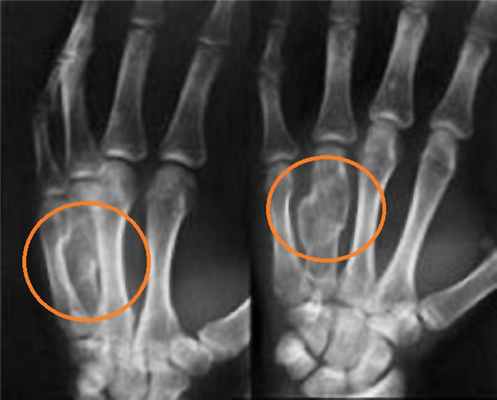

Большинство переломов дистального отдела лучевой диагностируются обычной рентгенографией в 2-х проекциях. Компьютерная томография (КТ) необходима при внутрисуставных переломах.

Для подтверждения диагноза выполняются рентгенограммы лучезапястного сустава в 2-х проекциях. Рентген являются наиболее распространенным и широко доступным диагностическим методом визуализации костей.

Рентгеноанатомия суставов кисти

При рентгеновском исследовании кисти хорошо видны сочленяющиеся кости и рентгеновские суставные щели всех суставов (рис. 90). Рентгеновская суставная щель лучезапястного сустава расширена у медиального края за счет для рентгеновского излучения суставного диска у головки локтевой кости. Только гороховидная кость накладывается на трехгранную; остальные кости запястья видны отдельно, вследствие чего суставные щели между ними четко контурируются. Рентгеновские суставные щели пястно-фаланговых, межфаланговых суставов выпуклой стороной направлены дистально.

Рентгенограмма правой кисти и лучезапястного сустава в прямой проекции:

A Ладьевидная кость (Os scaphoideum)

B Полулунная кость (Os lunatum)

C Трёхгранная кость (Os triquetrum)

D Гороховидная кость (Os pisiforme)

E Кость-трапеция (Os trapezium)

F Трапециевидная кость (Os trapezoideum)

G Головчатая кость (Os capitatum)

H Крючковидная кость (Os hamatum)